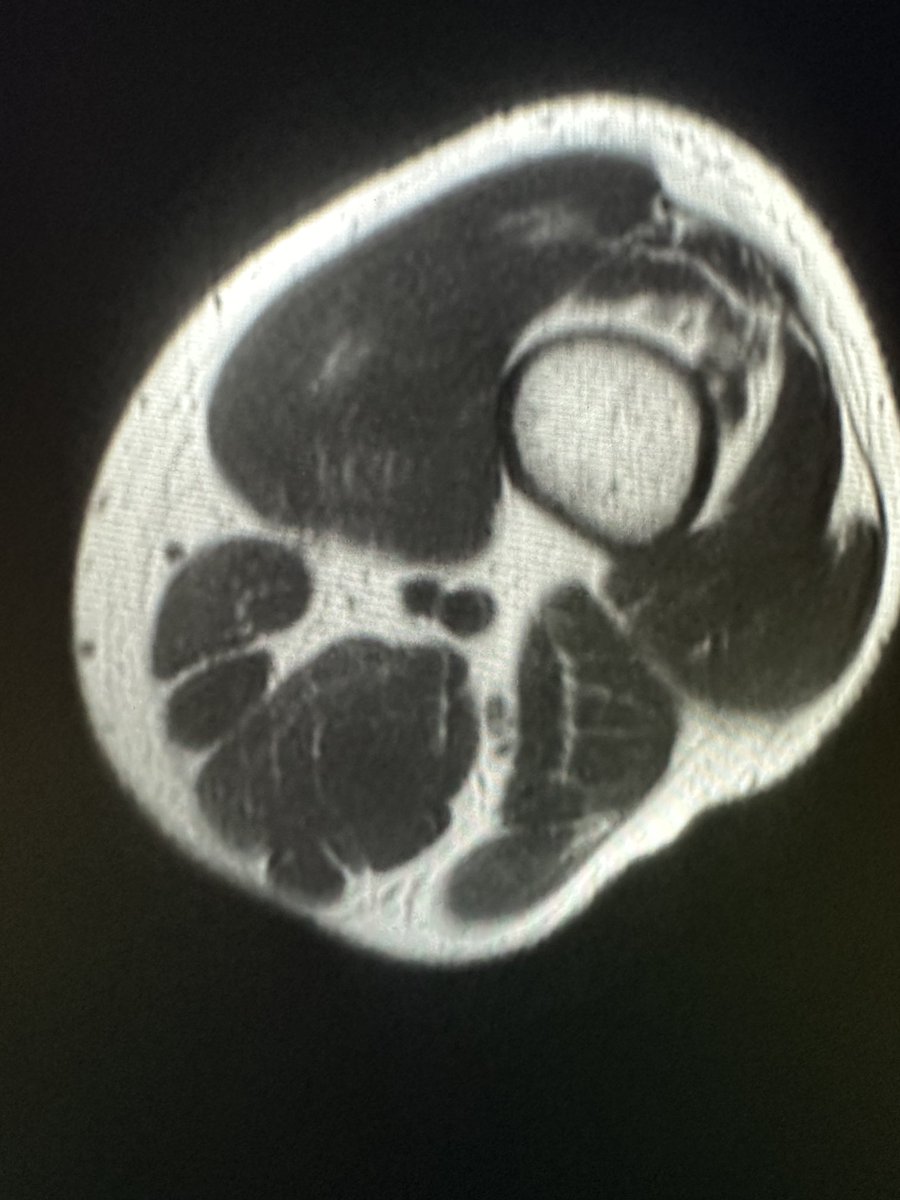

This study assesses MRI's utility in distinguishing lateral meniscal oblique radial tears from other meniscal tears in patients with ACL injury. ajronline.org/doi/10.2214/AJ…